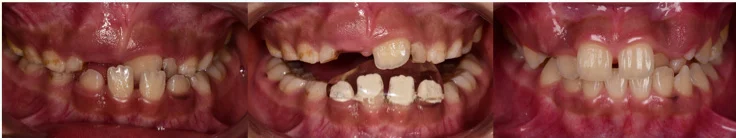

兒童在換牙期出現前牙錯咬時,若能儘早使用簡單的斜面咬合板治療, 百分之90以上的錯咬改正都可得到很好的效果,費用少,且時間短, 若沒在適當時間改善前牙錯咬,會因錯咬影響或限制小朋友顎骨的發育, 提前做一些處理,可以讓小朋友恢復正常的咬合關係, 也會減少將來矯正治療的難度。